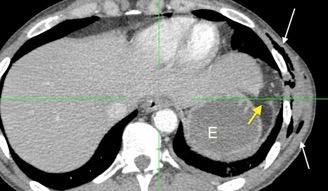

Recibe una puñalada en costado izquierdo

La laceración tiende a ocurrir en la unión

músculotendinosa . (64-90% en el lado izquierdo)

Diafragma “colgante” (“dangling sign”)

(“Dangling sign”)

TC. Mejor con multicorte. (reconstrucciones).

Asociación: Aire en pared.

Fracturas costal .Rotura esplénica. Neumoperitoneo.

Diafragma discontinúo Herniación de la grasa omental

Desser TS et al.The dangling diaphragm sign: sensitivity and comparison with existing CT signs of blunt traumatic diaphragmatic rupture. Emerg Radiol 2010